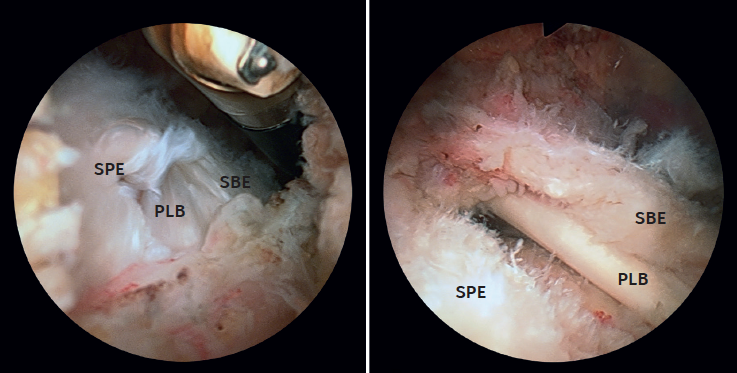

Figure 3. View from the posterior subacromial portal of type IB and IIB ruptures in left shoulders. A: type IB; B: type IIB. LPB: long portion of the biceps; SSC: subscapularis; SSP: supraspinatus.

The type I-A and II-A ruptures were repaired from the glenohumeral space via a posterior viewing portal and an AS portal. In type I-B and II-B ruptures, suturing of the lesion was carried out in the same way, but that of the SSP was completed from the subacromial space using a third anterolateral portal (Figure 3). The type I-A ruptures were usually repaired with a single anchoring, while the type I-B, II-A and II-B ruptures typically required two or three.